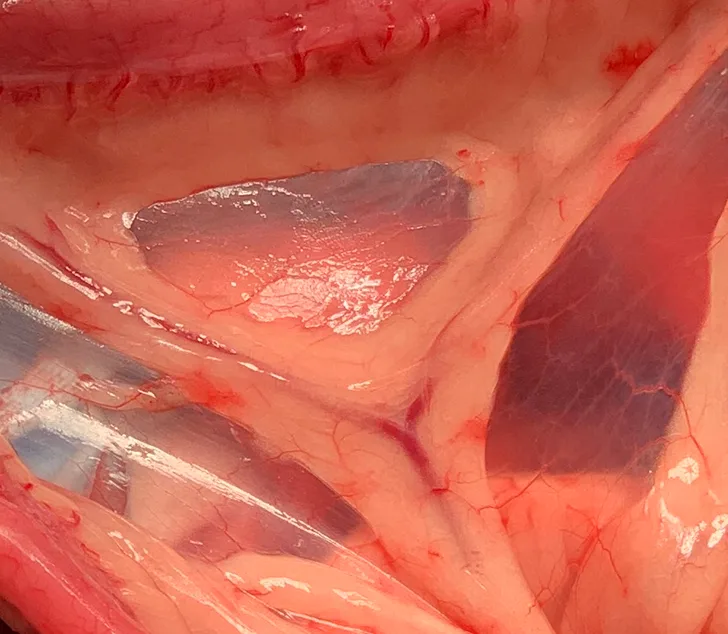

Gloved hands holding small intestine section that is telescoping into an enlarged adjacent section.

A portion of intestine after attempted jejuno-jejunal intussusception reduction. The intussusception could not be fully reduced.